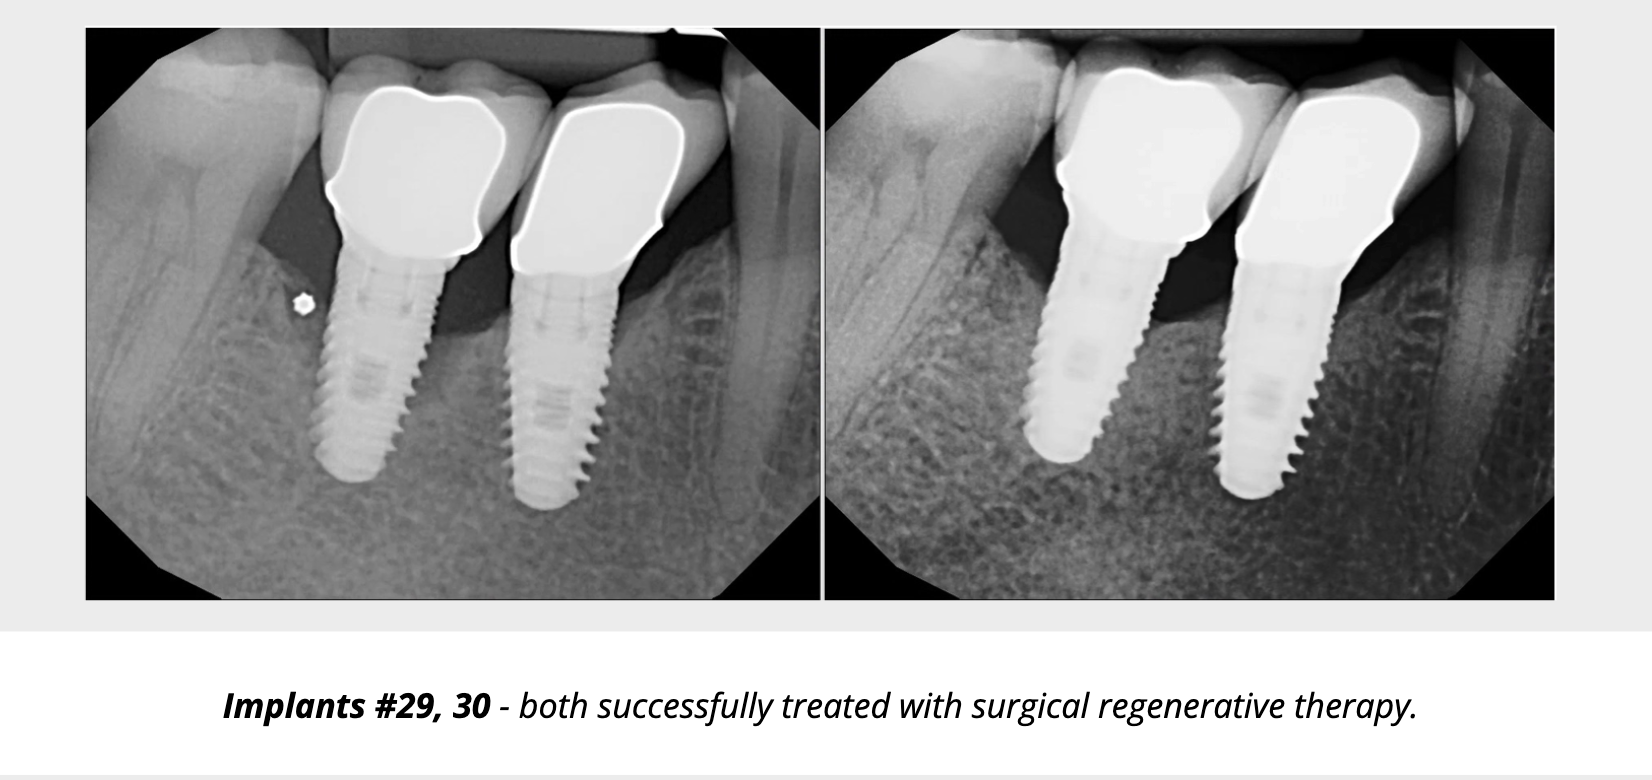

When inflammation progresses to bone loss, we enter the realm of peri-implantitis. The therapeutic goal expands: arrest bone loss, reduce probing depths, resolve inflammation, and ideally regenerate lost supporting structures. While non-surgical therapy is often the first line treatment for peri-implantitis, it has limited efficacy for moderate-to-severe cases. Surgical therapy is often required once non-surgical measures are insufficient. Flap access, debridement, implant surface decontamination, possibly resective or reconstructive surgery, often with grafting materials or membranes, are indicated. There is evidence that surgical therapy can reduce probing depths by 30-50%.